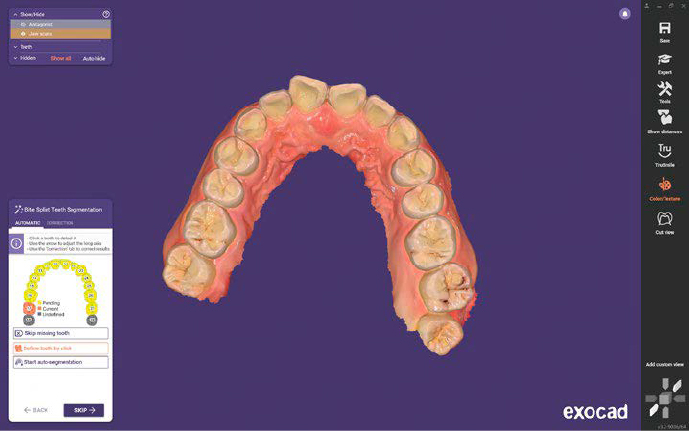

ESPORTAZIONE IN FORMATI APERTI

Esportazione semplice in formati universali per un’integrazione fluida con software CAD come Exocad, garantendo progettazioni protesiche senza vincoli